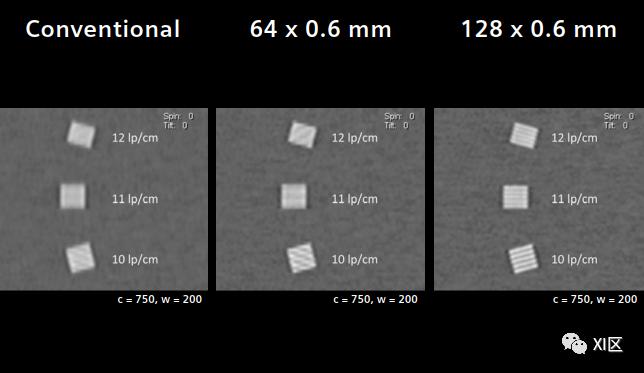

我们在常见的Catphan模体(The Phantom Laboratory, Salem, NY, USA)中使用每厘米1到21线对(lp/cm)的条形图,用无法提供最高分辨率数据的传统CT和64层、128层的SOMATOM Perspective测试z方向的可实现空间分辨率切片模式。

用于比较的传统模式是从一个典型的标称0.6 mm切片创建的,在许多供应商的系统中,实际半高宽为0.9 mm。根据国际电工委员会(IEC)的指南,实际薄片厚度与标称薄片厚度的偏差可达50%,因此,在许多其他供应商的系统中发现的薄片厚度可达0.9 mm,仍然可以指定为更薄的薄层。

64排/64层和64排/128层模式与具有0.6 mm标称层厚但在许多系统上实际半高宽仅为0.9 mm的传统模式相比。西门子Perspective128 x 0.6 mm IVR模式在z方向将空间分辨率提高到0.4 mm。

在SOMATOM Perspective上,使用小焦点SureView和IVR可以显著提高空间分辨率。与传统系统相比,128 x 0.6 mm IVR模式的z方向分辨率从0.5 mm或10 lp/cm提高到0.4 mm或12.5 lp/cm。